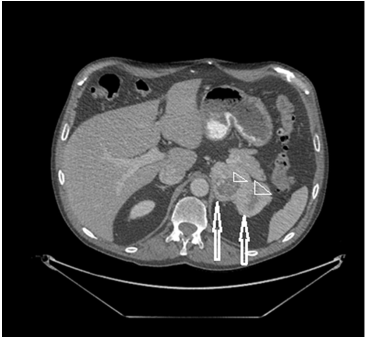

患者没有显示任何体重增加、虚弱或失眠的病史。性欲和毛发分布没有任何变化。有超过10年的高血压病史,由两种药物控制。体检显示生命体征正常,无库欣综合征症状,体重指数(BMI)正常。尿液中儿茶酚胺和皮质醇在正常范围内,血清醛固酮对肾素活性、电解质和硫酸脱氢表雄酮(DHEA-S)水平也在正常范围内。在第一次CT扫描后4个月,再次对腹部进行CT扫描,发现左侧肾上腺有一个9 x 5.5 cm的双叶不均匀肿块,中心低密度。可能为坏死(图1)。

图1. 图像显示左侧肾上腺有一个双叶肿块(两个箭头),大小为9 x 5.5厘米。中央有低密度的迹象表明坏死(两个箭头)